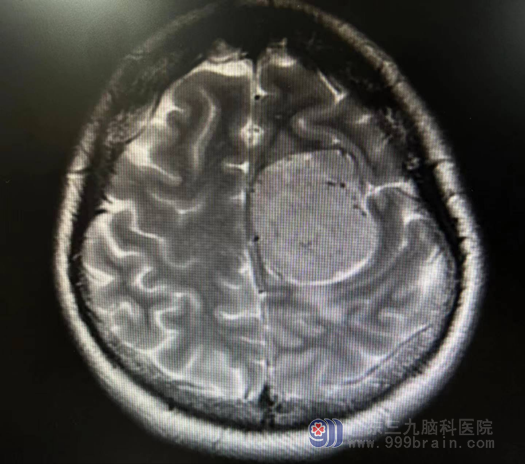

七月中旬,素来身体健康,来自佛山顺德区的朱女士,近五年余却反复头痛,休息后可缓解,曾在当地医院就诊过,考虑“颈椎病”。近2个月来患者无明显诱因出现右侧肢体乏力,2周前曾到当地医院就诊,查头颅MR示“左侧额部镰窦旁占位性病变”,考虑脑膜瘤,家人们紧张不已,为进一步检查和治疗,遂来我院就诊。我院神经外十科主任欧阳辉教授接诊患者后,详细耐心的询问病情后,结合MR检查结果,以“脑膜瘤”诊断收患者住院。

欧阳辉教授带领神经外十科医生团队,对患者进行详细的检查,并为患者制定了手术方案,在医生的沟通下,患者及其家属同意手术治疗。我科精准实施手术:采用全麻下行“左侧额部镰窦旁占位性病变切除+硬脑膜修补术+颅骨成型术”。在外十科手术团队、麻醉科、手术室的团结合作下,完整摘除了一颗“大荔枝”一样的肿瘤,术中、术后都很成功。